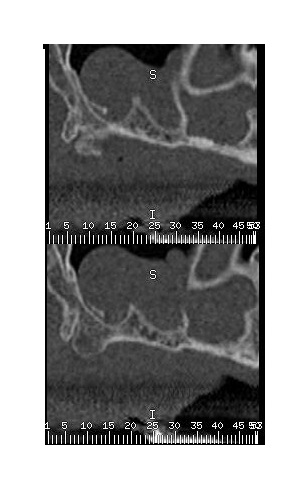

les scans donc.; sur la coupe 7 et 8 haut droite on voit un residu de je sais trop quoi, vraisemblablement l yperplasie est est due à cela..

Radiographiquement ca ressemble à un polype mais ce qui me gene c'est le residu qu'on voit dans le sinus. Si c'est la cause de l'inflammation, envoie ton patient chez l'ORL...c'est plus sure. tu as egalement de sacrés septa ton decollement ne sera pas evident.